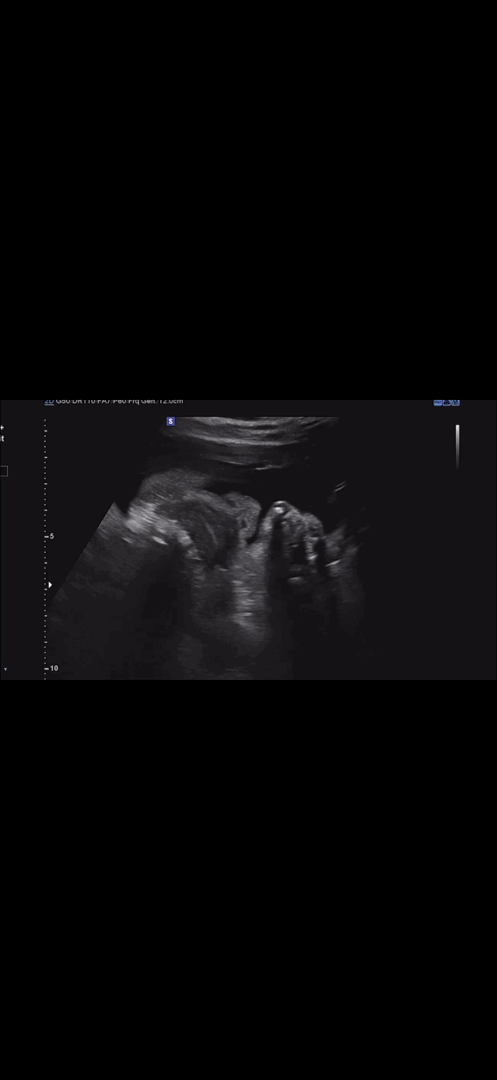

어머 코랑 입이랑 너무 이쁘네요 오물오물 귀여워라

막달검사갔다가 마조리카 닮은 딸 얼굴 영접

34주차 5일째라 막달검사랑 독감예방접종 맞고 왔는데 아기는 큰편이고.. 머리카락도 나고 입도 뻐끔뻐끔하고 혀도 보여줬어요 근데 입술이 영락없는 마조리카 캐릭터랑 똑같이 생겨서 웃음만 나오고요ㅋㅋㅋㅋㅋ 주수보다 큰 내 애기보고 지금 포케 시켰어요😅 아 ! 손마디랑 관절이 너무 아픈데 부어서 그런거라고 저염식으로 먹으라 하시더라구요? 다른 베동 엄마들도 혹시 손마디 아프면 참고해요